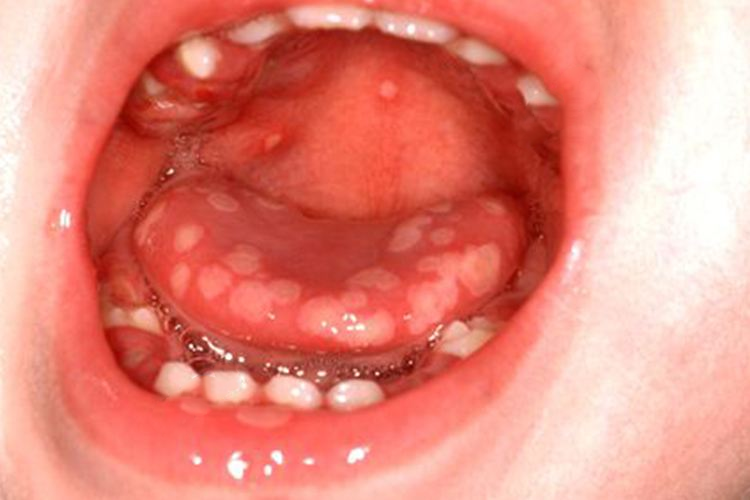

小孩舌头有小泡泡的症状可见于疱疹性口炎、复发性阿弗他溃疡、手足口病等,可根据其具体症状区分判断。

小孩舌头有小泡泡可能为疱疹性口炎,机体初次感染多发生于2-3岁小孩,临床表现为黏膜充血、水肿,会出现成簇的小水疱,并伴有咽痛、发热等全身症状。病理特点为上皮内会形成疱疹,上皮下方呈现炎症样改变。

多数手足口病患者为急性起病。发病前或发病同时有发热,主要侵犯手、足、口、臀等部位;其疱疹呈圆形或椭圆形扁平凸起,内有混浊液体,有不痛、不痒、不结瘢的特征,因口中有溃疡,患儿会有流涎、拒食的现象。